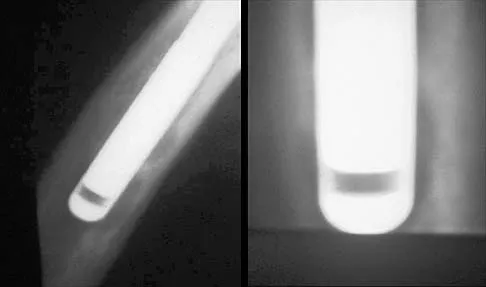

Figure 33 shows the AP and lateral radiographs of an obese 58-year-old man who underwent a cementless total hip arthroplasty 6 years ago. He reports no pain, and examination reveals a normal gait and painless hip range of motion. What is the most likely diagnosis?

Explanation